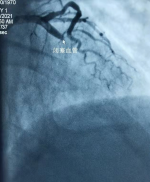

田道华:让头痛不再“头痛”